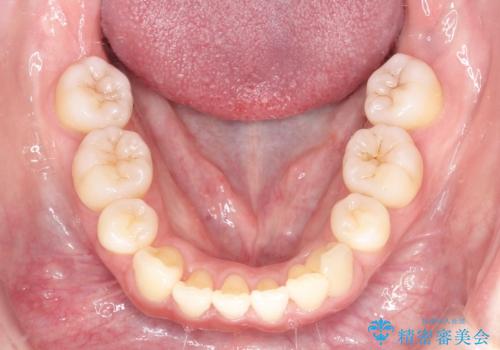

【審美装置】癒合歯がある方の治療

- 前歯の前突を主訴に来院されました。

下の前歯は癒合歯がある珍しいケースです。

治療に関しては小臼歯を4本抜歯して前歯を下げるような計画を立てて治療しました。

抜歯スペースの移動量を調整するために、矯正用アンカースクリューや親知らずを活用して治療を行いました。